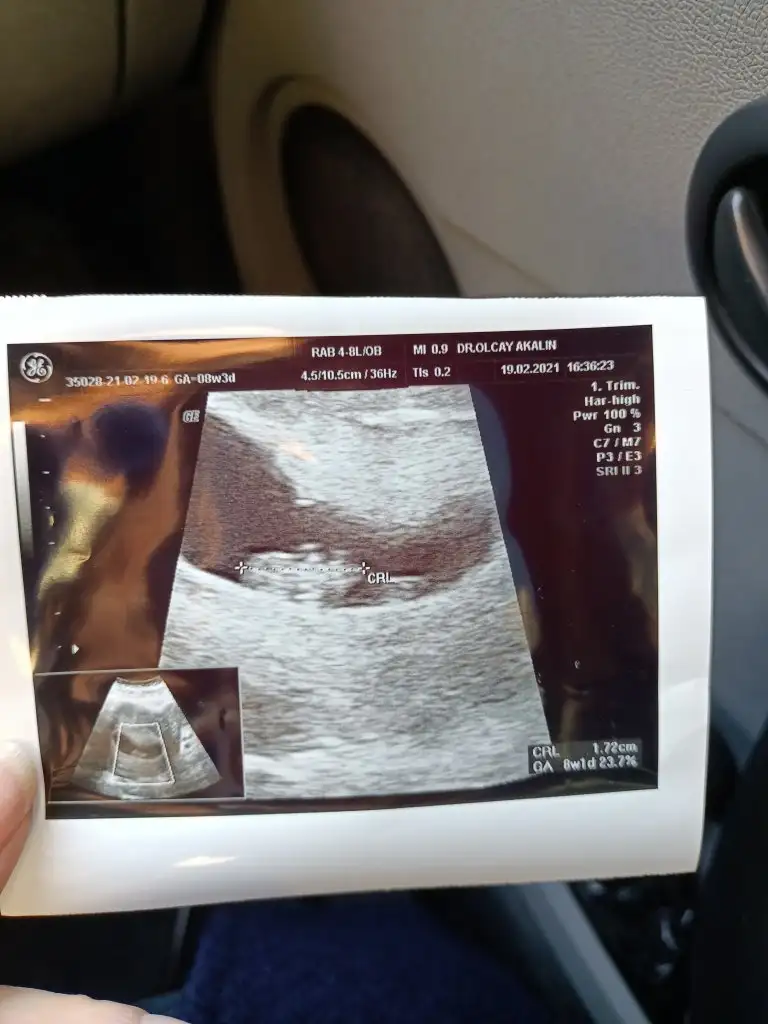

Nazal kemik çok belirgindi ölçüm yapmadı ense 0.93 çıktı çok şükür inşallah kan sonucu da güzel gelirÇok sevindim ense burun kaç çıktı acaba